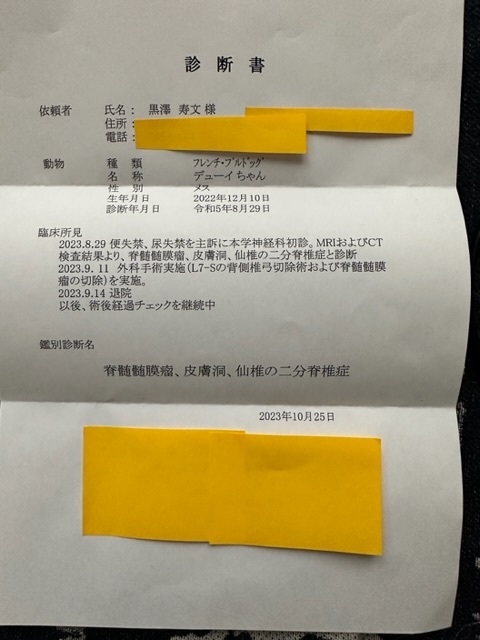

※上記は大学病院で頂いた診断書

※下記は初診かつ、会陰形成術をして頂く動物病院より発行して頂いた診断書、治療計画書

二分脊椎症、脊骨迶骨迶膜瘤 441.490円

会陰形成術 130.824円

合計572.314円